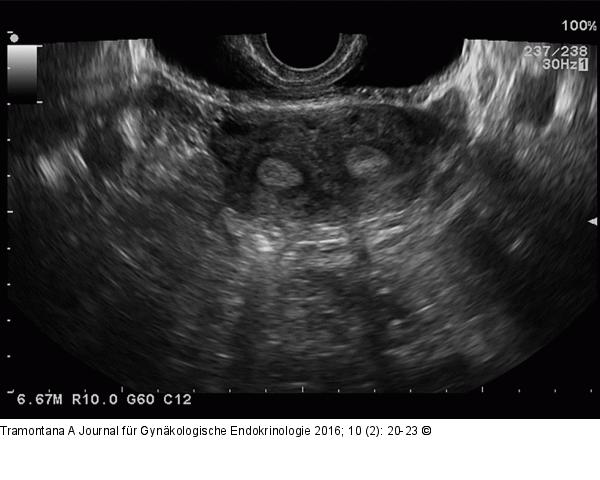

Abbildung 3: Uterus subseptus

Sonographische Darstellung des Katzenaugenphänomens. |